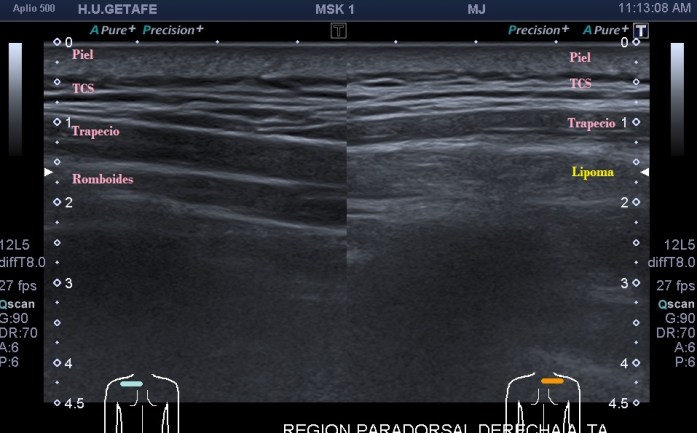

Como hoy quiero que este post sea muy visual y de poca lectura te voy a mostrar los diferentes lugares claves y básicos para que puedas estar atenta en las exploraciones para buscar líquido en estas localizaciones. Primera imagen de normalidad, segunda imagen de «no normalidad» y anatomía y ordenada según la clasificación que has visto un poco más arriba.